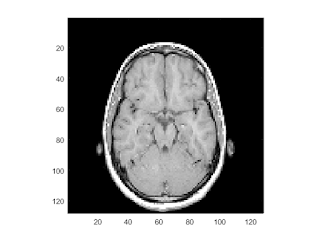

example to display MRI image and data

close all; % Clear all windows clear all; % Clear all variables clc; % Clear console % load the data and transform the data array from 4-D to 3-D % The MRI data, D, is stored as a 128-by-128-by-1-by-27 array. % Use the squeeze command to remove 4-D to 3-D. % The result is a 128-by-128-by-27 array load mri D = squeeze(D);

display one of the MRI images

figure

colormap(map)

image_num = 10;

image(D(:,:,image_num))

axis image

x = xlim;